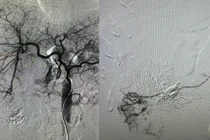

Ê -kíp can thiệp của BSCKI Lê Tiến Hưng, Phó Trưởng Khoa Chẩn đoán hình ảnh và điện quang can thiệp thực hiện nút mạch cấp cứu u gan vỡ - Ảnh BVCC

Ê - kíp can thiệp của BSCKI Lê Tiến Hưng, Phó Trưởng Khoa Chẩn đoán hình ảnh và điện quang can thiệp đã tiến hành chụp mạch bằng hệ thống chụp mạch số hóa xóa nền DSA để xác định chính xác vị trí động mạch gan bị tổn thương gây chảy máu và bơm chất tắc mạch để cầm máu.

Kết quả kiểm tra ngay sau nút mạch đã không còn tình trạng chảy máu vùng gan tổn thương. Sau can thiệp 24h, người bệnh thoát nguy kịch, chỉ số sinh tồn ổn định, được điều trị hồi sức tích cực tại Khoa Hồi sức tích cực Ung bướu, Bệnh viện Bãi Cháy. Sau 10 ngày điều trị, sức khỏe bệnh nhân phục hồi tốt.